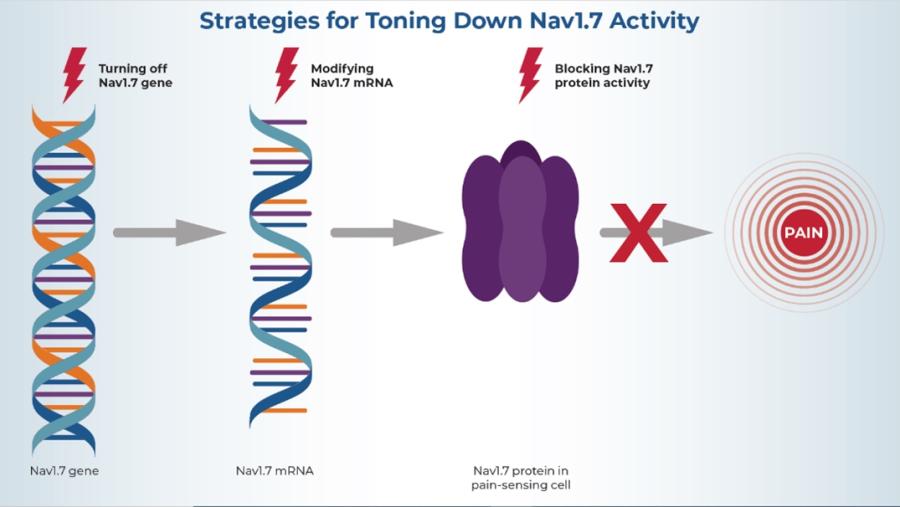

Image

Researchers hope that by turning off or toning down Nav1.7 activity, they can silence pain-sensing cells and thus relieve pain.